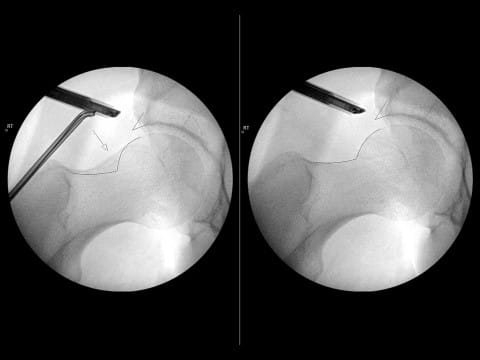

Dr. Salata performs the first stage of the surgery, using arthroscopic techniques to round the femoral head, improve offset and repair labral damage resulting from FAI. The Director of the Joint Preservation and Cartilage Restoration Center and Division Chief of Sports Medicine at University Hospitals Cleveland Medical Center, he is also a Professor at the School of Medicine and Associate Orthopedic Team Physician for the Cleveland Browns.

The first University Hospitals orthopedist to perform arthroscopic hip procedures, Dr. Salata has completed over 4,000 of the minimally invasive surgeries. “There is a pretty substantial learning curve to both parts of this procedure — the more experienced the hands, the better the outcomes,” he says. “It has taken time to establish a program that offers excellence throughout the journey for patients, including specialized inpatient nursing care and physical therapy protocols.”